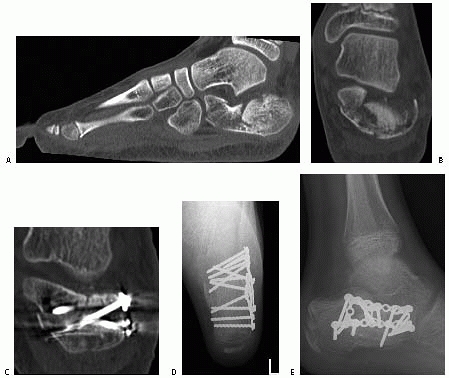

the fractured calcaneus. Not only does it clearly show the fracture

lines and altered anatomy, but also reveals injuries to adjacent bones.

Sanders et al.146 have used CT scans

to develop a classification system that is particularly useful in the

preoperative planning of open reduction of these fractures. The primary

and secondary fracture lines are identified and the degree of

communition and position of the fragments is more accurately seen than

in the radiographs. The primary fracture line usually runs obliquely

from plantar-medial to dorsolateral exiting the posterior facet.

Secondary fracture lines that develop off this primary line are also

seen and their pattern determines the classification of the fracture (Fig. 27-15).

The CT scan also allows a three-dimensional reconstruction to be made

which again is useful in visualizing the fracture lines for possible

internal fixation.

reviewed 9 patients with 10 calcaneal fractures and performed CT scans

on all of them. They found the fracture patterns in these adolescents

(average 13.4 years old) to be very similar to those found in adults.

They did find less communition in children than in adults, even though

the children reportedly had fallen from greater heights.

![]() |

|

FIGURE 27-20 Intra-articular depressed fracture of the calcaneus in a 13-year-old boy. A. Preoperative sagittal CT shows the depression of the posterior facet into the body of the calcaneus. B. Coronal CT shows the displacement of the frature fragments. C. Postoperative CT scans are useful at checking the fracture reduction and length and position of the screws. D,E. Postoperative radiographs confirm restoration of the Böhler angle.